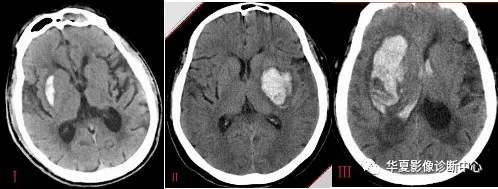

丘脑出血show

图片尺寸3508x2480